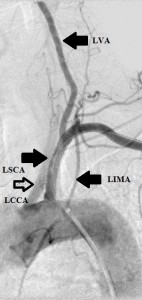

Key: LVA, left vertebral artery; LSCA, left subclavian artery; LCCA, left common carotid artery; LIMA, left internal mammary artery.

The 4 images you see above were recorded by me during primary stenting of irregular atherosclerotic stenosis of the left subclavian artery in a 54-year-old Hispanic female who was referred to my interventional radiology clinic for management of the stenosis. She had presented to her primary care physician with symptoms of hindbrain ischemia upon using her left upper limb and earlier workup confirmed left subclavian arterial stenosis. The 2 top images illustrate the character and severity of her disease, the first image in the bottom row shows the process of balloon-expandable stenting of the disease, while the 2nd image in the bottom row reveals complete elimination of the stenosis and reappearance of the left vertebral and internal mammary arteries, which were invisible on the pre-intervention angiograms reflecting the severity of the stenosis.